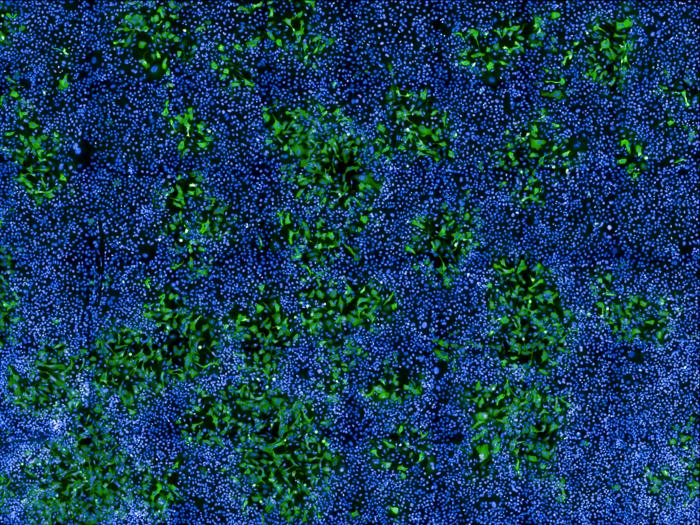

IMAGE: HUMAN CELLS INFECTED WITH MPXV (IN GREEN) AMONG UNINFECTED CELLS (NUCLEI IN BLUE). IMAGE TAKEN WITH A CONFOCAL MICROSCOPE. view more

CREDIT: © MATHIEU HUBERT AND OLIVIER SCHWARTZ, INSTITUT PASTEUR.